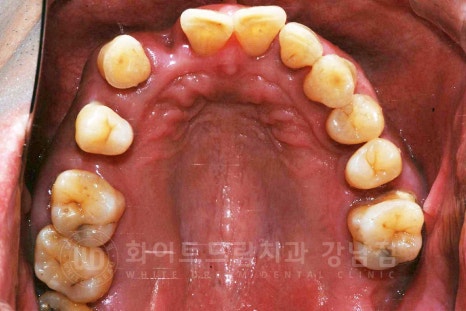

환자분은 치주염으로 대다수의 치아가 흔들리는 상태셨으며

지인의 추천으로 저희 강남 화이트드림치과를 찾아주신

40대의 남성분이셨습니다.

초진 x-ray 사진을 보면 많은 치아들이 있는 상태이지만

치아를 잡고 있는 잇몸뼈 면적이 적은 것이 확인됩니다.

정상적인 상태는 잇몸뼈가 치아의 2/3 정도를 덮고 있는 상태인데

환자분은 치주염으로 골 흡수가 많이 진행되어 있어

대부분의 치아가 흔들리고 있는 상태였습니다.